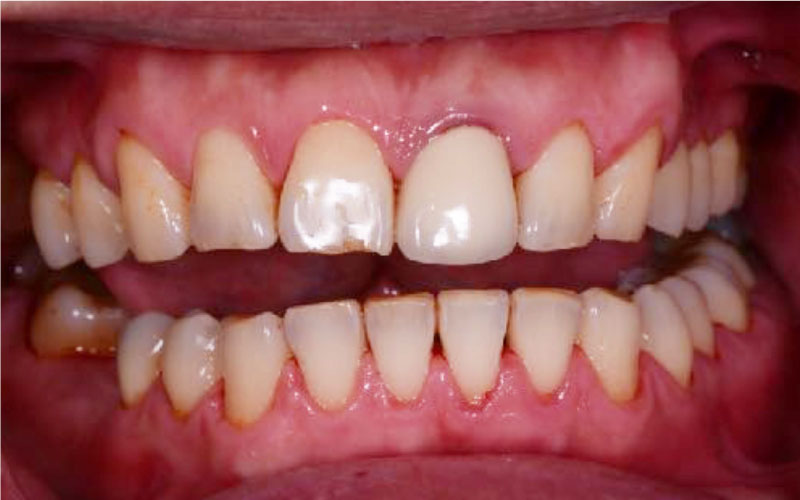

美白前

美白後